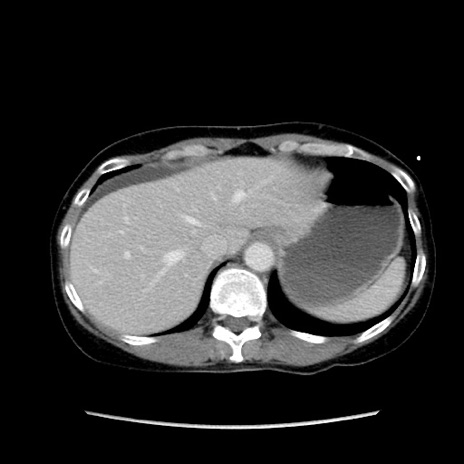

症例32(横断像)

【症例】40歳代 女性

【主訴】上腹部痛、嘔気・嘔吐

【現病歴】約9時間前頃から急に上腹部痛、嘔気、嘔吐が出現。改善しないため救急要請。

【既往歴】子宮頚癌(広汎子宮全摘術、放射線療法)、腸閉塞

【身体所見】腹部:平坦、軟、腸雑音亢進、上腹部を中心に腹部全体に圧痛あり。

【データ】WBC 8400、CRP 0.03